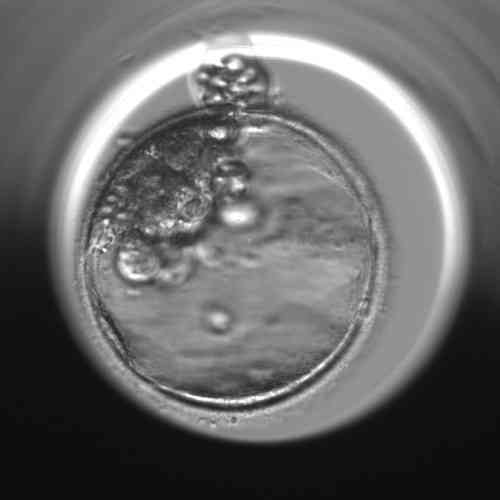

Am fünften Tag entwickeln sich die Embryonen bis zum Blastozystenstadium

Im Stadium der embryonalen Blastozyste sind die Zellen des Embryos bereits in den Embryoblasten (innere Zellmasse – ICM), aus dem der Embryo selbst entsteht, und das Trophoektoderm – Trophoblast, aus dem sich die Plazenta und die Amnionmembranen entwickeln, unterteilt. Im Inneren der Blastozyste befindet sich ein mit Flüssigkeit gefüllter Hohlraum, die Blastozele.

Das derzeit am weitesten verbreitete System zur morphologischen Beurteilung von Blastozysten ist das Gardner Grading System. Morphologische Beurteilung bedeutet, dass jede Blastozyste danach kategorisiert wird, wie ihre einzelnen Bestandteile – Embryoblast, Trophoektoderm und Blastocoel – unter dem Mikroskop aussehen.

- Schlüpfende Blastozyste, deren Hülle (Zona pellucida) bei weiterem Volumenwachstum reißt und einige Zellen des Trophoectoderms nach außen wandern.